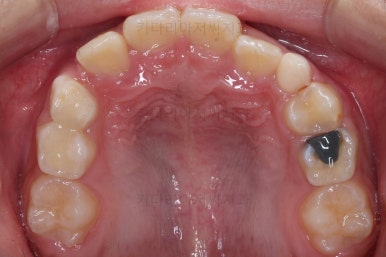

무려 4개월 만에 부산어린이교정 치료가 종료되었습니다.

앞니의 교합이 매우 안정적이여서 치료를 끝냈고요.

전후 비교해 보겠습니다.

반대교합이 완벽히 개선되면서 주걱턱으로 보였던 얼굴형태도 완벽히 개선되었고요.

한 쪽으로 치우치던 아래턱의 위치도 돌아오면서 비대칭이 개선되었습니다.

심지어는 위아래 앞니가 삐뚤었던 부분도 일정 부분 좋아졌습니다.

반대교합으로 인해 아래 앞니 잇몸 퇴축이 있었던 부분은 되돌아오지는 않는 점이 아쉽습니다.